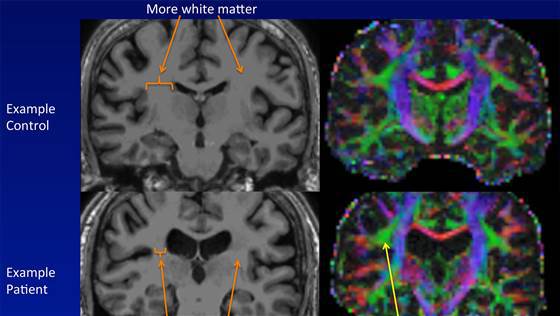

Savanţii au utilizat trei tehnici diferite de imagistică prin rezonanţă nucleară, pentru a obţine o analiză care să permită măsurarea dimensiunilor diferitelor zone ale creierului, pentru a observa substanţa albă a creierului, compusă din fibrele nervoase care transportă mesaje între neuroni, şi pentru a măsura fluxul sangvin cerebral.

Analizarea datelor obţinute a arătat că persoanele care suferă de SOC au un volum de substanţă albă mai redus, dar şi o răspândire anormală de molecule de apă într-o regiune a substanţei albe din emisfera cerebrală dreaptă.

De asemenea, cercetătorii au descoperit la pacienţii cu SOC anomalii în cele două regiuni ale creierului care conectează lobul frontal cu lobul temporal.